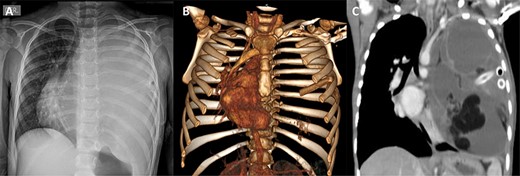

(A) Preoperative chest X-ray showing total atelectasis of the left lung and deviation of the cardiac silhouette to the right. (B) Postoperative Day 9 chest X-ray after total resection of the teratoma, showing re-expansion of the left lung

The patient underwent a total resection of the mediastinal mass via a median sternotomy. Given the extension of the teratoma and adhesions to the chest wall, an additional approach with a left anterior thoracotomy was made (Fig. 2). Entry into the pleural space was performed through the sixth intercostal space to obtain safe visualization of the cavity and proceed to tumor excision. Many adhesions were found to the thoracic wall, diaphragm and phrenic nerve. Additionally, a nutritional artery depending on left internal mammary artery was discovered with collateral veins draining to brachiocephalic vein. A section of the left internal mammary vessels, dissection of the phrenic nerve, ligation of the nutritional vessel, mediastinal tumor excision, ligation of the thymic vessels and thymectomy was performed. Thoracic drainage tubes (two) were placed. The mediastinal tumor, excised in block, was red–gray colored, well circumscribed and capsuled with a size of 15 × 15 × 20 cm. Postoperatively, the collapsed left lung was re-expanded, and the patient was extubated on Day 1 (Fig. 3). The patient recovered from the operation and was discharged on the ninth postoperative day. Preoperative atelectasis of the left lung partially resolved, and the pathological examination revealed a benign mature teratoma with cystic degeneration. Anatomical pathology test showed the presence of glandular epithelial cells concomitant with the presence of cartilage tissue (Fig. 4) The histochemistry test revealed CD3(+) CD20(+) TDT(−) CD5(−) cells. Thymic tissue was negative for malignancy; nine lymph nodes showed reactive follicular hyperplasia.